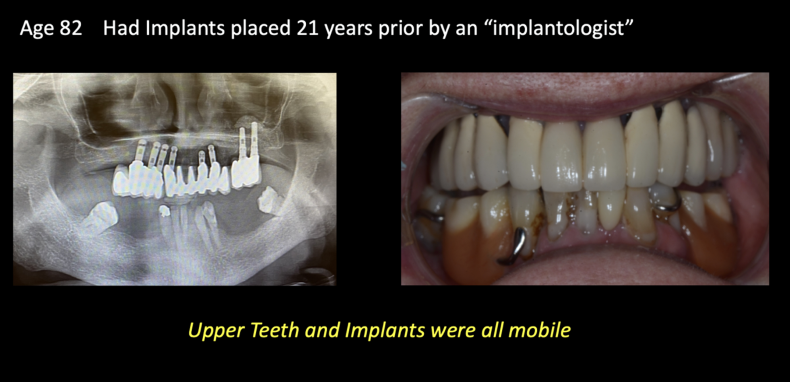

- Ability to use Zygoma implants for treatment for a mouth full of failing implants

Zygomatic Implants have equal success with traditional implants. Modern technology has improved all implant treatments in general. Traditional success rates for implant-supported prosthetics (bridges) approximate 95% after 25 years.

Factors affecting their success are proper placement for hygiene, surgical execution and planning. Importantly, is prosthesis designed, so it is easy to clean at home.

Regular appointments with a dental hygienist are recommended to clean the areas that you cannot get with your home hygiene. When patients follow their dentist’s advice and guidelines, Zygomatic implant treatment and their prosthesis can last a lifetime.